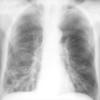

Bronchiectasis

Case 8 PA

Date: 06/06/2004

Views: 6319